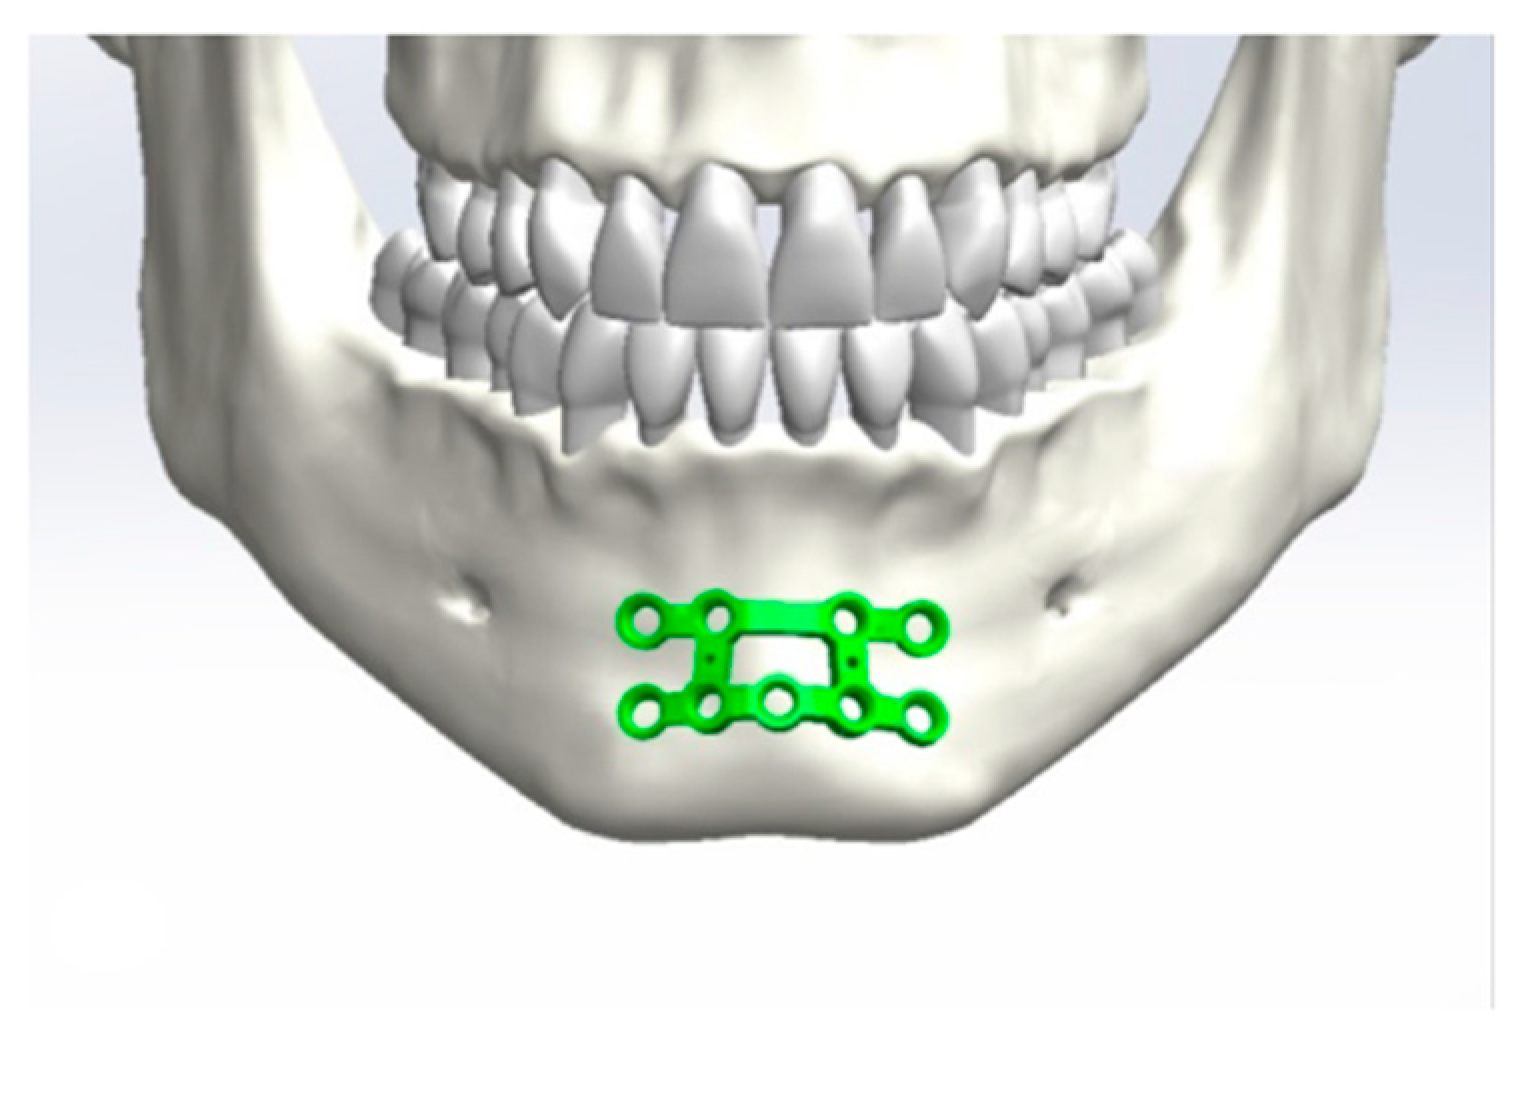

2.1. Design of the Plates

Application of the Plates